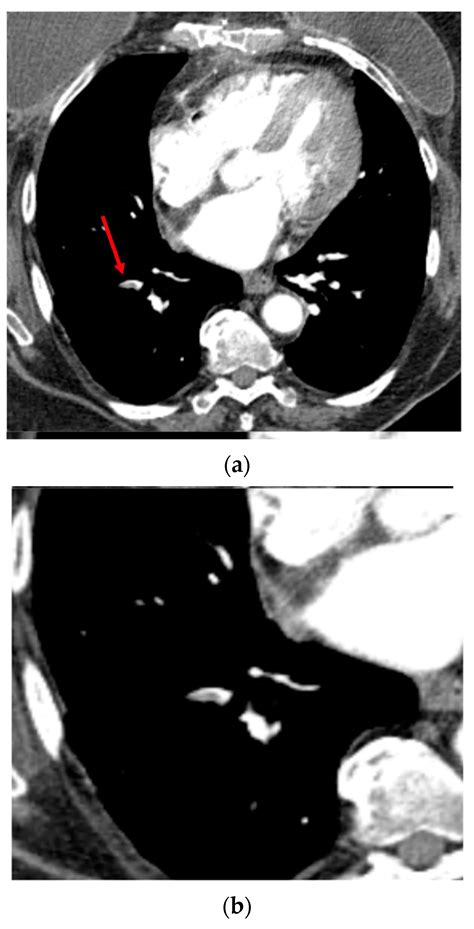

Understanding the CTA medical term is crucial for anyone involved in healthcare, whether you are a medical professional, a student, or someone interested in medical terminology. CTA stands for Computed Tomography Angiography, a diagnostic imaging procedure that combines a CT scan with an injection of contrast material to produce detailed images of blood vessels. This technique is invaluable for diagnosing various conditions, particularly those related to the cardiovascular system.

Computed Tomography Angiography (CTA) is a non-invasive medical test that uses X-rays and contrast material to create detailed images of blood vessels. These images help doctors diagnose and treat various conditions, including:

CTA is particularly useful for evaluating the blood vessels in the brain, heart, kidneys, and other parts of the body. The procedure is quick, painless, and provides high-resolution images that can be analyzed in multiple planes.

• Cardiovascular Imaging: CTA is used to evaluate the coronary arteries for blockages, aneurysms, and other abnormalities. It is particularly useful in diagnosing coronary artery disease.

• Neurological Imaging: CTA can detect aneurysms, blood clots, and other vascular abnormalities in the brain. It is often used in emergency settings to diagnose stroke.